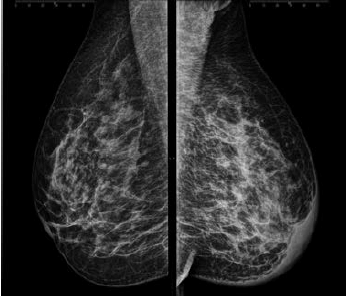

Assinale a alternativa que apresenta corretamente o que observa-se na análise das imagens da mamografia.

Uma paciente de 46 anos realizou esta mamografia.

Assinale a alternativa que contém a descrição e a classificação BIRADS correspondente.